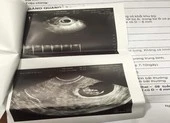

Sau khi hút mỡ bụng, chị A. rơi vào trạng thái chóng mặt, buồn nôn, khó thở nên vào một bệnh viện trên địa bàn Hà Nội. Các bác sĩ phát hiện chị A. đang mang thai khoảng tám tuần tuổi. Sau đó chị A. đến làm việc với Thẩm mỹ viện Sophie International nhưng nơi đây chưa giải quyết thỏa đáng.